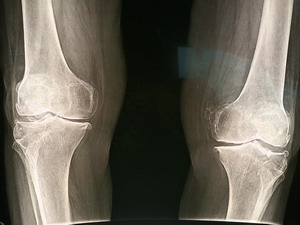

Best exercise for knee osteoarthritis

So is it cardio, weights, stretching, balance, mind-body? After comparing 200 studies the winner is aerobic training like walking, bicycling, or swimming. They were twice as effective as the next runner up, strength training.